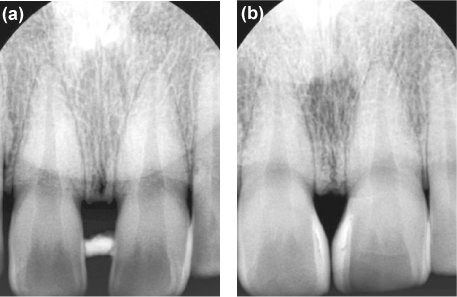

Figure 2The length was obtained from the ratio, comparing values of radiograph and the cast.

A small piece of a temporary radiopaque material (Caviton, GC, Tokyo, Japan) was located between the teeth for the landmark of determining the proper position of the contact point. Periapical radiographs were taken by using a paralleling technique with a film holder (XCP,Dentsply-Rinn, Elgin, IL, USA). Files were transferred to a personal computer and examined with a resolution of 1,024 × 768 pixels (

Figure 2a). The length from the most coronal portion of the crestal bone to the radiopaque material was measured with the Photoshop CS2. Also, the length from the bottom of the radiopaque material to incisal edge of the central incisors was measured.

A study model was fabricated to measure the actual length between the top of the papilla and incisal edge of the central incisors. The actual length between the crestal bone and the top of papilla was calculated using a proportional expression. The actual papilla length was 3.97 mm (

Figure 2b). Based on the distance, the contact point was defined approximately 5.0 mm from the bone crest. The study model was mocked up so that a plan of proposed esthetic treatment could be presented to the patient. The analysis of the length and the width of the upper central incisors demonstrated an unfavorable proportion after the closure with composite resin (

8 A soft temporary radiopaque restorative material, periapical radiographs and study model were used to verify the papilla length. Based on such a distance, the contact point was defined as being at approximately 5.0 mm from the bone crest.

10 A rubber stop was used to indicate the penetration depth of the needle in the tissue. But, this method is needed to anesthetize, and is painful. The method using a soft temporary radiopaque restorative material and periapical radiographs is non-invasive and more useful. Lee et al. validated a method of measuring the length of the interdental papilla non-invasively, using radiopaque material and a periapical radiograph.

11 They used a 5 mm metal ball attached to the teeth for reference material. Martegani et al. used a self-made resin device carrying the 5 mm radiographic metal piece.7 In this case, the actual length of study model was used to verify magnification. Study model was also used for a correct diagnosis and treatment planning.